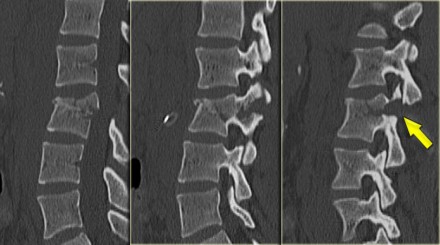

What is unique about the Chance fracture is the horizontal orientation, which is nicely demonstrated on the sagittal reconstructions on the left.

Continue with the coronal reconstructions.

Also on the coronal reconstructions we can see the horizontal orientation of the fracture.

On the left a Chance variant.

This is a pure ligamentous injury, which is analogous to bilateral interfacet dislocation, which is also a pure ligamentous injury.

There is rupture of the interspinous ligament, dislocation of the facet joints and a horizontal rupture of the disc.

Pure ligamentous and combined osseous / ligamentous variants have an increased risk of instability compared to the osseus type.

Always look for a split of the posterior elements, disc widening or widening of the spinous processes and facets.